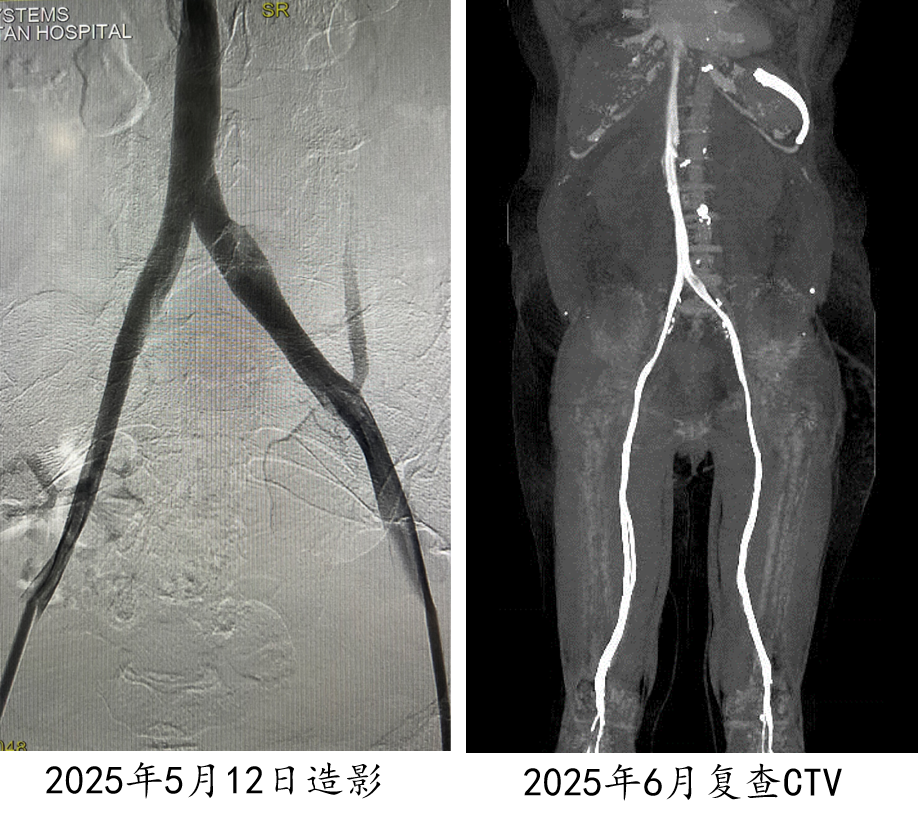

★ Case2:滤器相关慢性血栓闭塞开通后KISS支架

髂静脉支架置入术后研究:PTS中远期通畅率并不高

对于部分年轻患者,采取首期多次重复球囊扩张的策略。基于“闭塞通常发生在术后1-1.5个月”的观察,他们在第一次治疗后的1个月、1个半月左右进行二次、三次扩张。初步数据显示,这种策略能使一年期的血管通畅率超过70%,为患者保留了宝贵的自体血管通路,避免了过早植入支架。

图:Ⅰ期多次重复球囊扩张治疗结果

图:早期复查结果比较满意(一年期通畅率>70%)